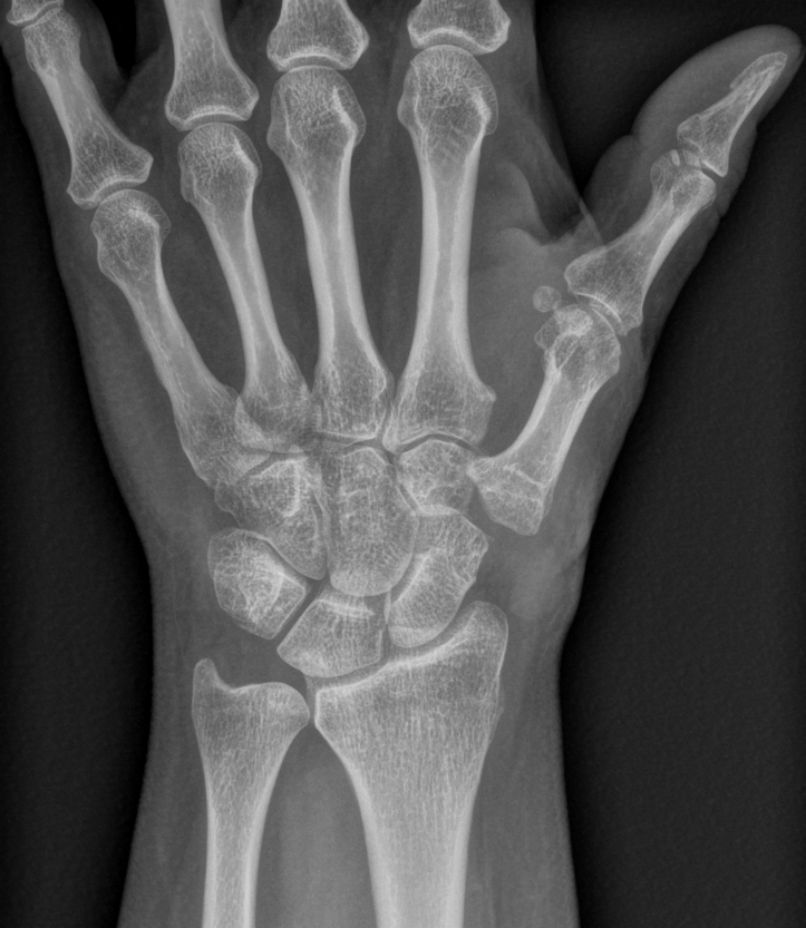

Les radiographies de face et de profil du pouce et les incidences de Kapandji confirment le diagnostic clinique et permettent d'apprécier l'importance de la destruction articulaire. On recherche également une atteinte arthrosique des autres articulations de la main.

Radiographie de rhizarthrose — arthrose du pouce

Le diagnostic est clinique : la douleur à la base du pouce et la perte de force lors de la pince orientent immédiatement, et la radiographie confirme l'arthrose. Les radiographies de face et de profil du pouce, complétées par les incidences spécifiques de Kapandji, permettent d'apprécier l'importance de la destruction articulaire et la subluxation associée. Le bilan radiologique recherche également une atteinte arthrosique des autres articulations de la main, qui est fréquente. Aucun autre examen complémentaire n'est nécessaire au diagnostic.